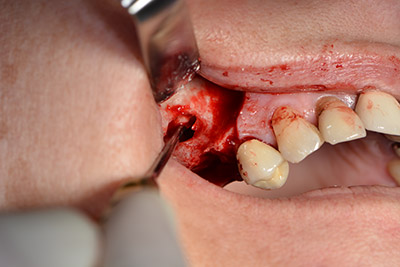

Le vie indicate di seguito sono realizzate con una perforazione a velocità ridotta, pari a 300 rpm. In questa fase Implantmed dimostra la sua grande affidabilità. È possibile predefinire il protocollo chirurgico: per selezionare le varie posizioni, basta premere la lettera “P” con il controllo a pedale (da fig. 10 a 11).

Il passaggio successivo consiste nel posizionamento dell'impianto, che nel nostro studio prevede una potenza pari a 32 Ncm (fig. 12).

Quindi, abbiamo optato per il rialzo del pavimento sinusale con impianto simultaneo. Implantmed è preimpostato sulla prima posizione per quanto riguarda la fenestrazione buccale della parete del seno mascellare.

La fenestrazione è impostata su 35.000 rpm, mentre la mucosa nasale viene preparata in direzione craniale (da fig. 13 a 14).